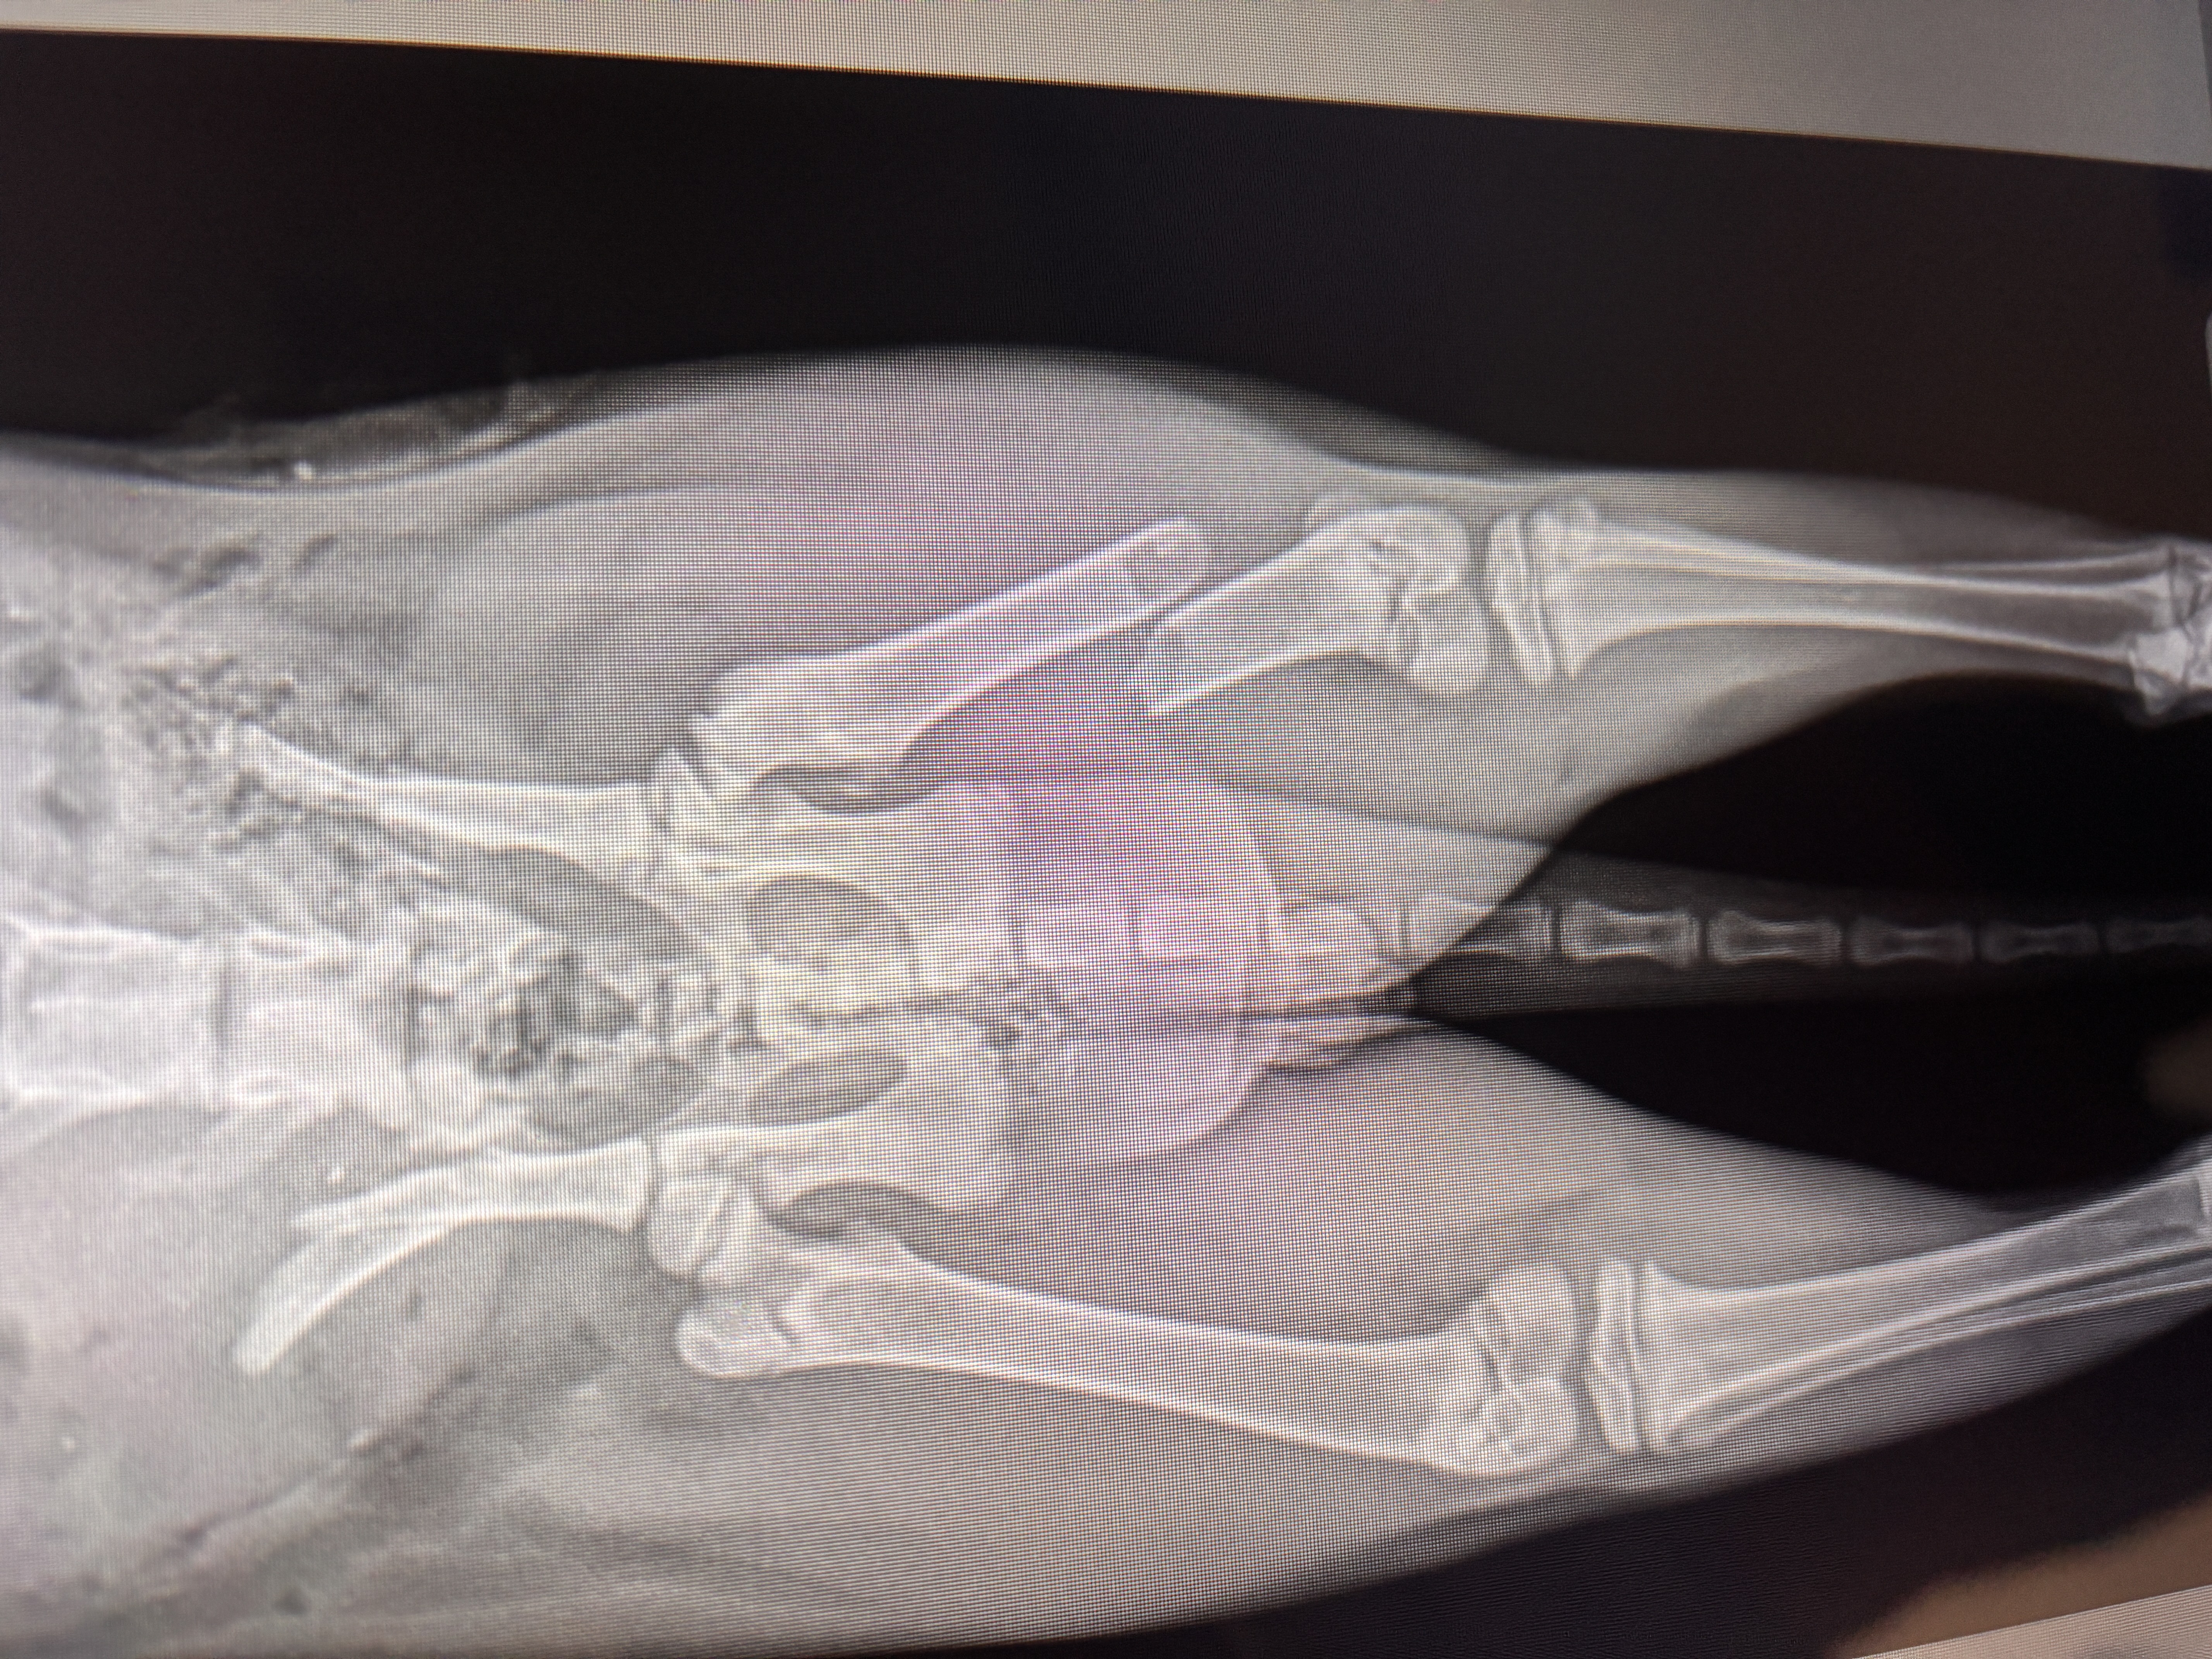

Dragon